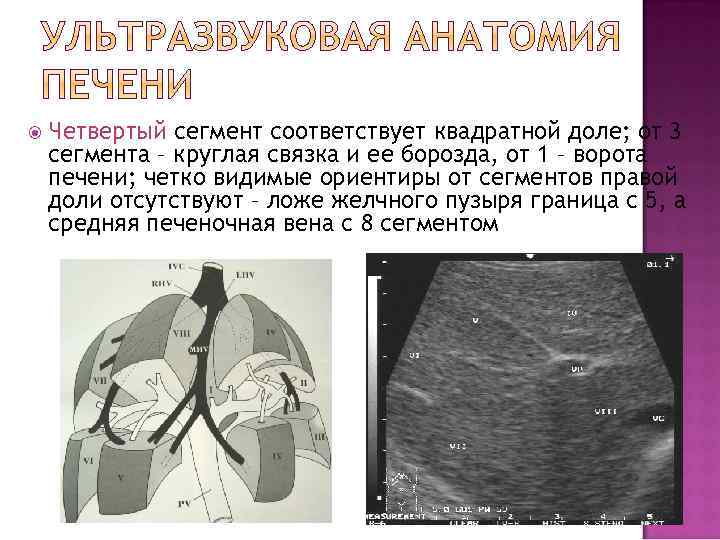

Четвертый сегмент соответствует квадратной доле; от 3 сегмента – круглая связка и ее борозда, от 1 – ворота печени; четко видимые ориентиры от сегментов правой доли отсутствуют – ложе желчного пузыря граница с 5, а средняя печеночная вена с 8 сегментом